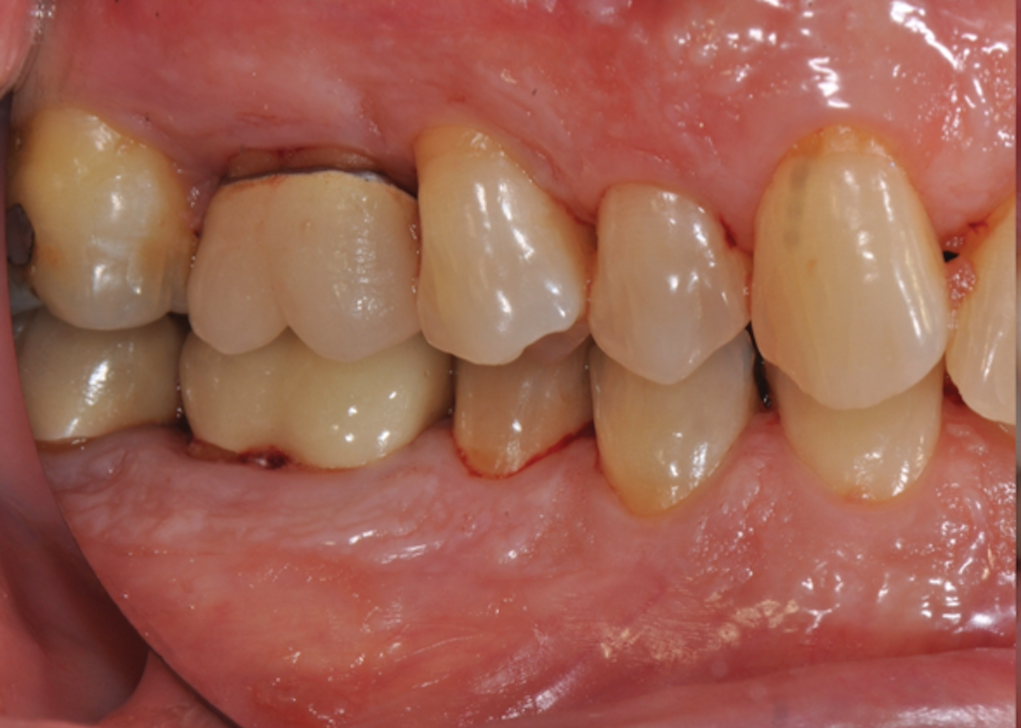

Fig 4. Pretreatment views: right lateral (Fig 2), frontal (Fig 3), and left lateral (Fig 4). Note: The maxillary right first molar (tooth No. 3) (Fig 2) would be identified as the most periodontally involved molar that was planned to be maintained.

Figure 4

Periodontal examination revealed generalized BOP and PDs up to 9 mm in the maxillary and mandibular molars with multiple furcations in each molar (Figure 2 through Figure 7). He presented with class I mobility in many posterior teeth and class II mobility in teeth Nos. 3 and 9 (maxillary right first molar and maxillary left central incisor, respectively). The periodontist decided to score tooth No. 3 for the PRS, as this was the most periodontally involved molar that was planned to be treated and maintained (Figure 2 and Figure 8). This tooth (maxillary right first molar = score 1) presented with probing depths of 7 mm (score 1); three total furcation invasions (score 3) (mesial [degree II furcation], buccal [degree I furcation], and distal [degree II furcation]); and a class II mobility (score 2). The total PRS for tooth No. 3 was 8, representing a "guarded" prognosis. Based on this score, the likelihood of not losing any teeth to periodontal disease for 15 years was 81%, and for 30 years the likelihood was just 56% (Figure 9).7